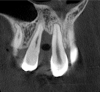

Tomographic images revealed a large tridimensional defect, with vertical and horizontal loss of bone extending to the apical third of teeth Nos. 6 and 8. Additionally, a buccal bone dehiscence was evident on tooth No. 5, and thin labial plates secondary to the orthodontic movement were present in several areas (Figure 3 and Figure 4).

Fig 3. Tomographic images revealed a tridimensional defect extending to the apical third of teeth Nos. 6 and 8, a buccal bone dehiscence on tooth No. 5, and associated thin labial plates.

Figure 3

Fig 4. Tomographic images revealed a tridimensional defect extending to the apical third of teeth Nos. 6 and 8, a buccal bone dehiscence on tooth No. 5, and associated thin labial plates.

Figure 4